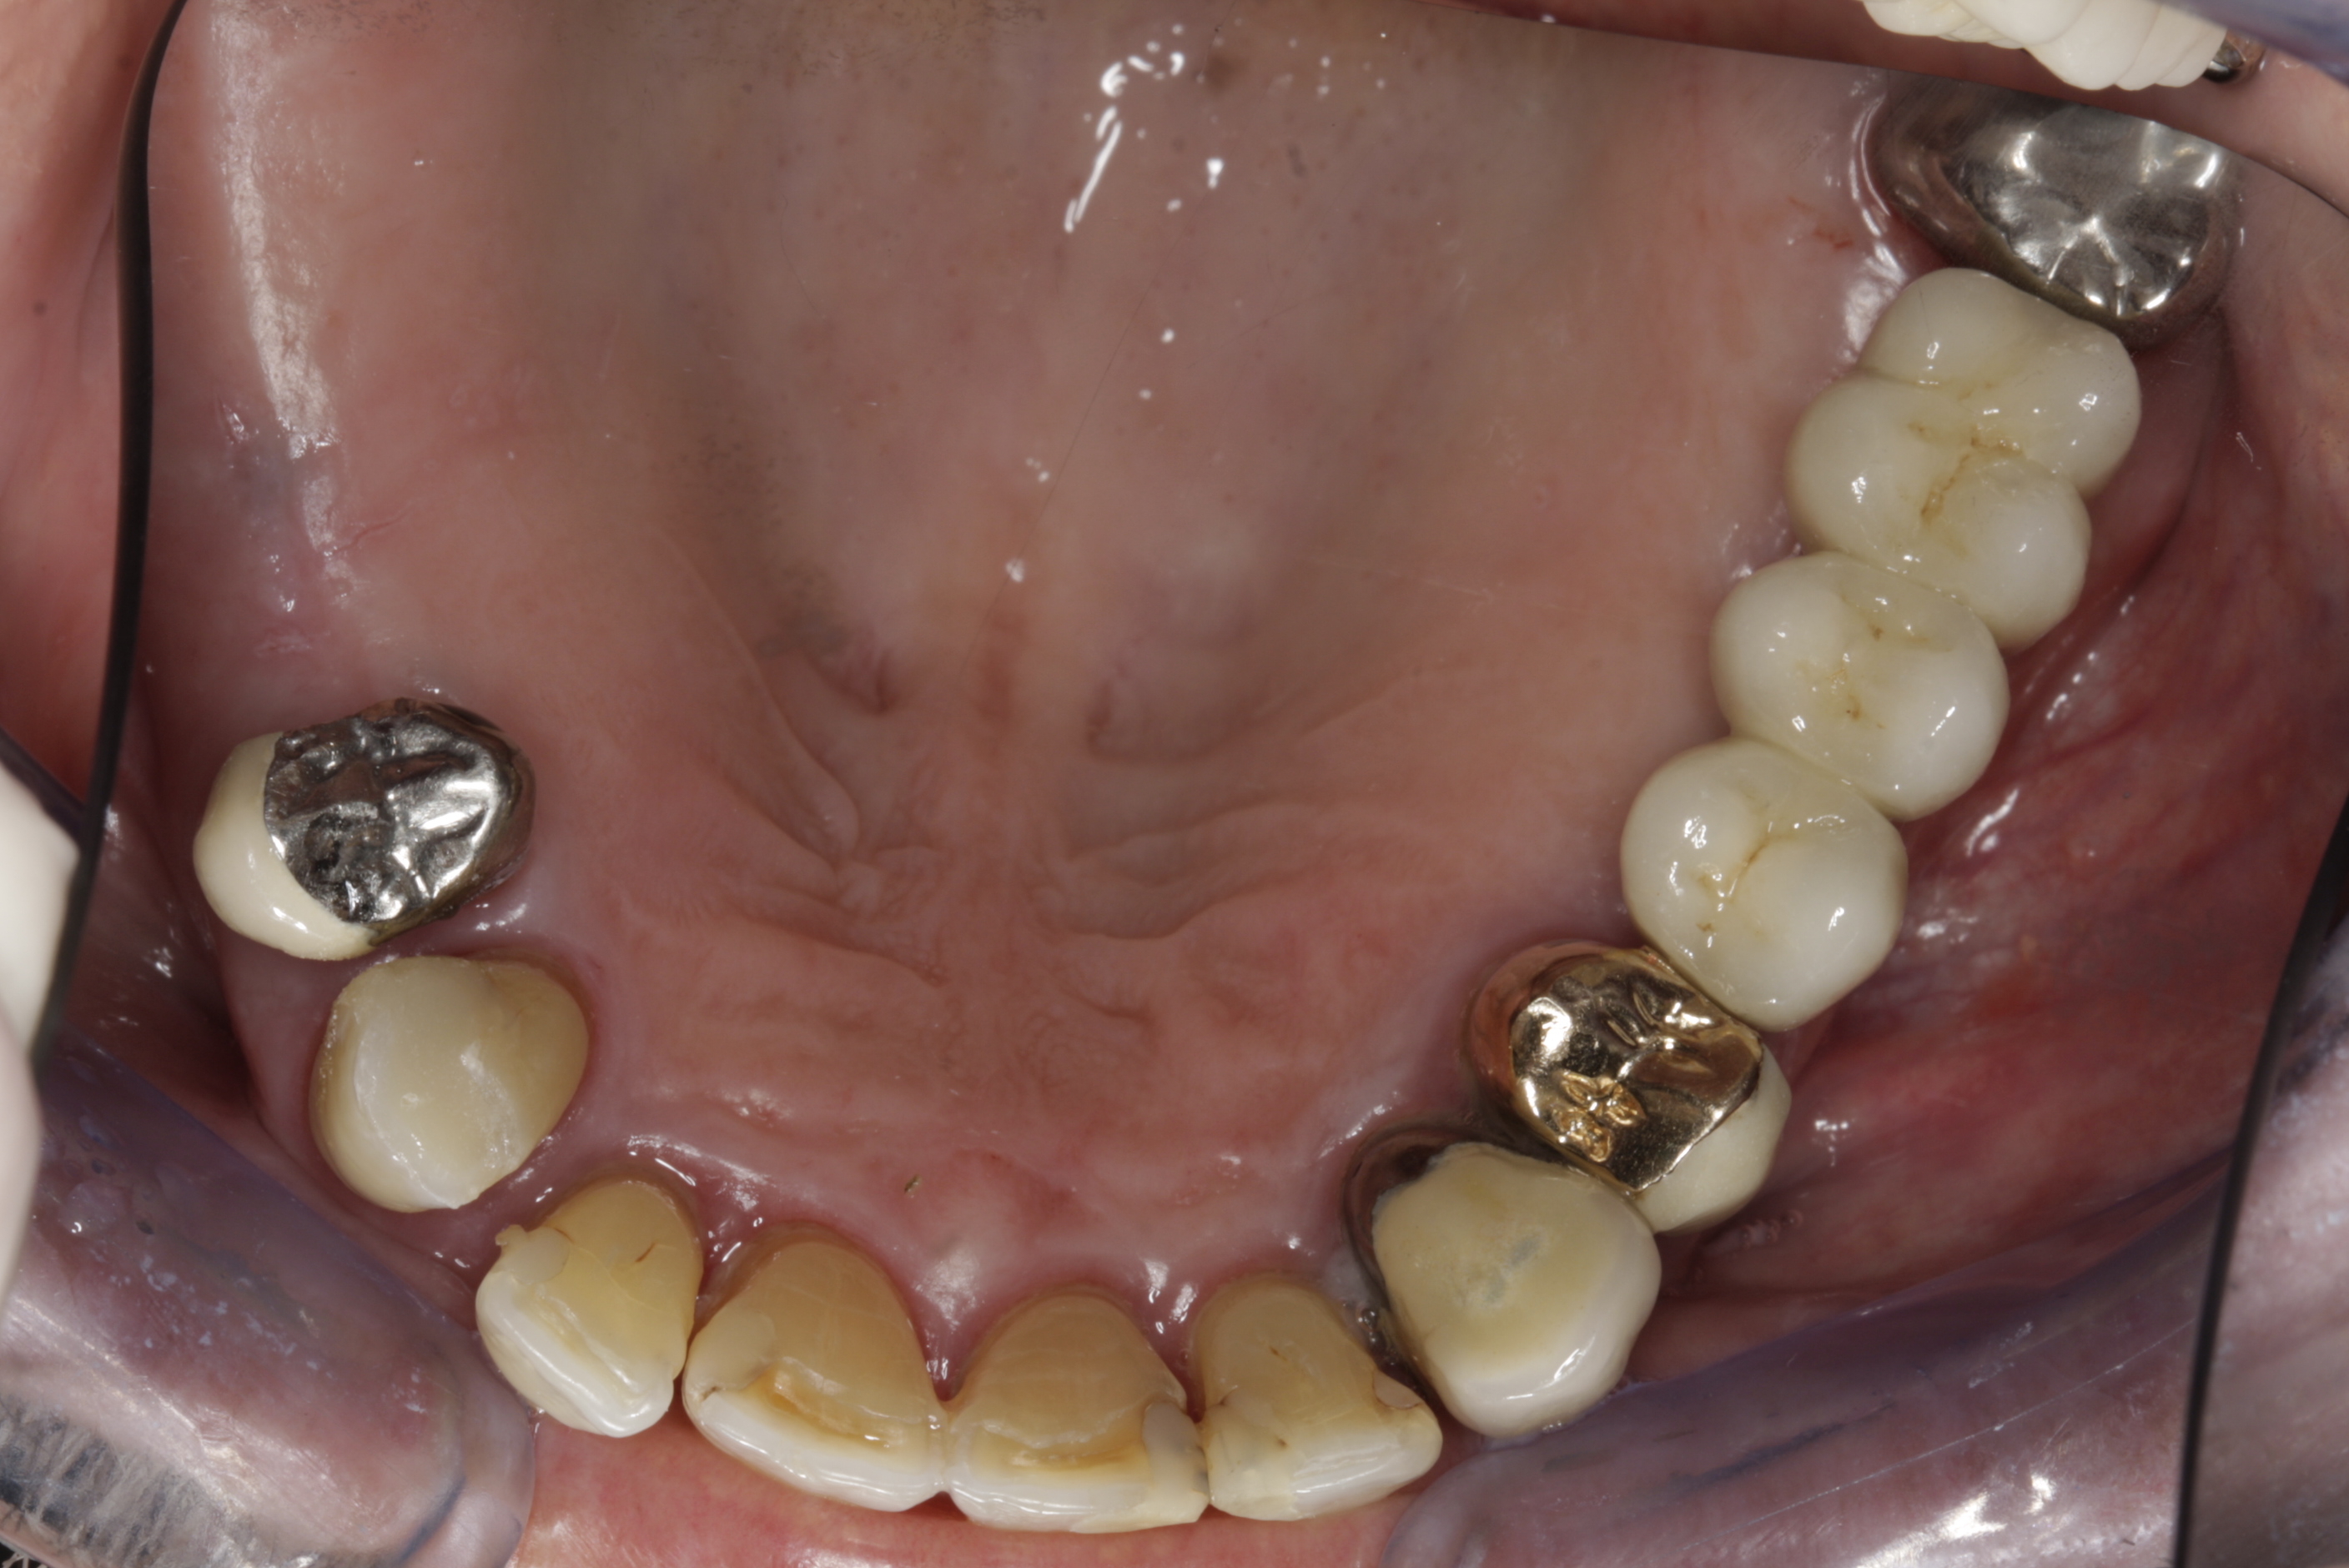

Částečně ozubená čelist

V případě chybění většího počtu zubů v postranních úsecích čelistí je možné ošetření pomocí implantátů, které nahradí ošetření pomocí snímacích náhrad kotvených na zbývajících zubech nebo patře.

Podmínkou je opět dostatečné množství kosti.

Protetické řešení může být pomocí můstku, který je kotvený na implantátech nebo pomocí jednotlivých korunek na implantátech.

V zásadě je možné do těchto můstků zařadit i přirozené zuby, zejména pokud je potřeba tyto zuby ošetřit proteticky – korunkami. Korunky nebo můstky mohou být na implantáty nacementovány nebo přišroubovány.

Zdravé zuby zůstanou zachovány a přitom náhrady jsou pevné, jako na vlastních zubech

Během let může postupnou ztrátou zubů zůstat v ústech omezený počet zubů, které umožňují držení zubních náhrad.

V důsledku přetížení zbylých zubů např. houpavými pohyb snímacích náhrad dochází k uvolnění těchto zubů a držení můstků a protéz je tak velmi těžké. V těchto případech můžeme pomocí implantátů zvýšit počet pilířů a tím zabránit přetěžování a ztrátě zbylých zubů